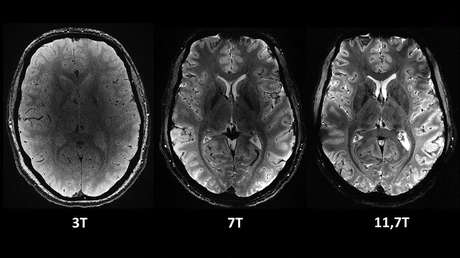

La resonancia magnética más potente del mundo muestra sus primeras imágenes